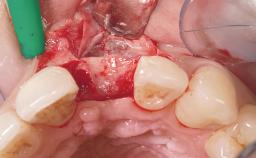

A 36-year-old female patient was referred for the replacement of the upper left central incisor (tooth 21), which had fractured. Although the tooth had been asymptomatic for many years, the crown began to loosen, at which time she presented to her dentist for an assessment. Teeth 21 and 22 had both been endodontically treated many years previously. She was a healthy individual and a non-smoker.

The crown of tooth 21 was splinted to the adjacent teeth with composite resin, and the gingiva was inflamed.

| Bone Volume | Deficient horizontally, requiring prior grafting |